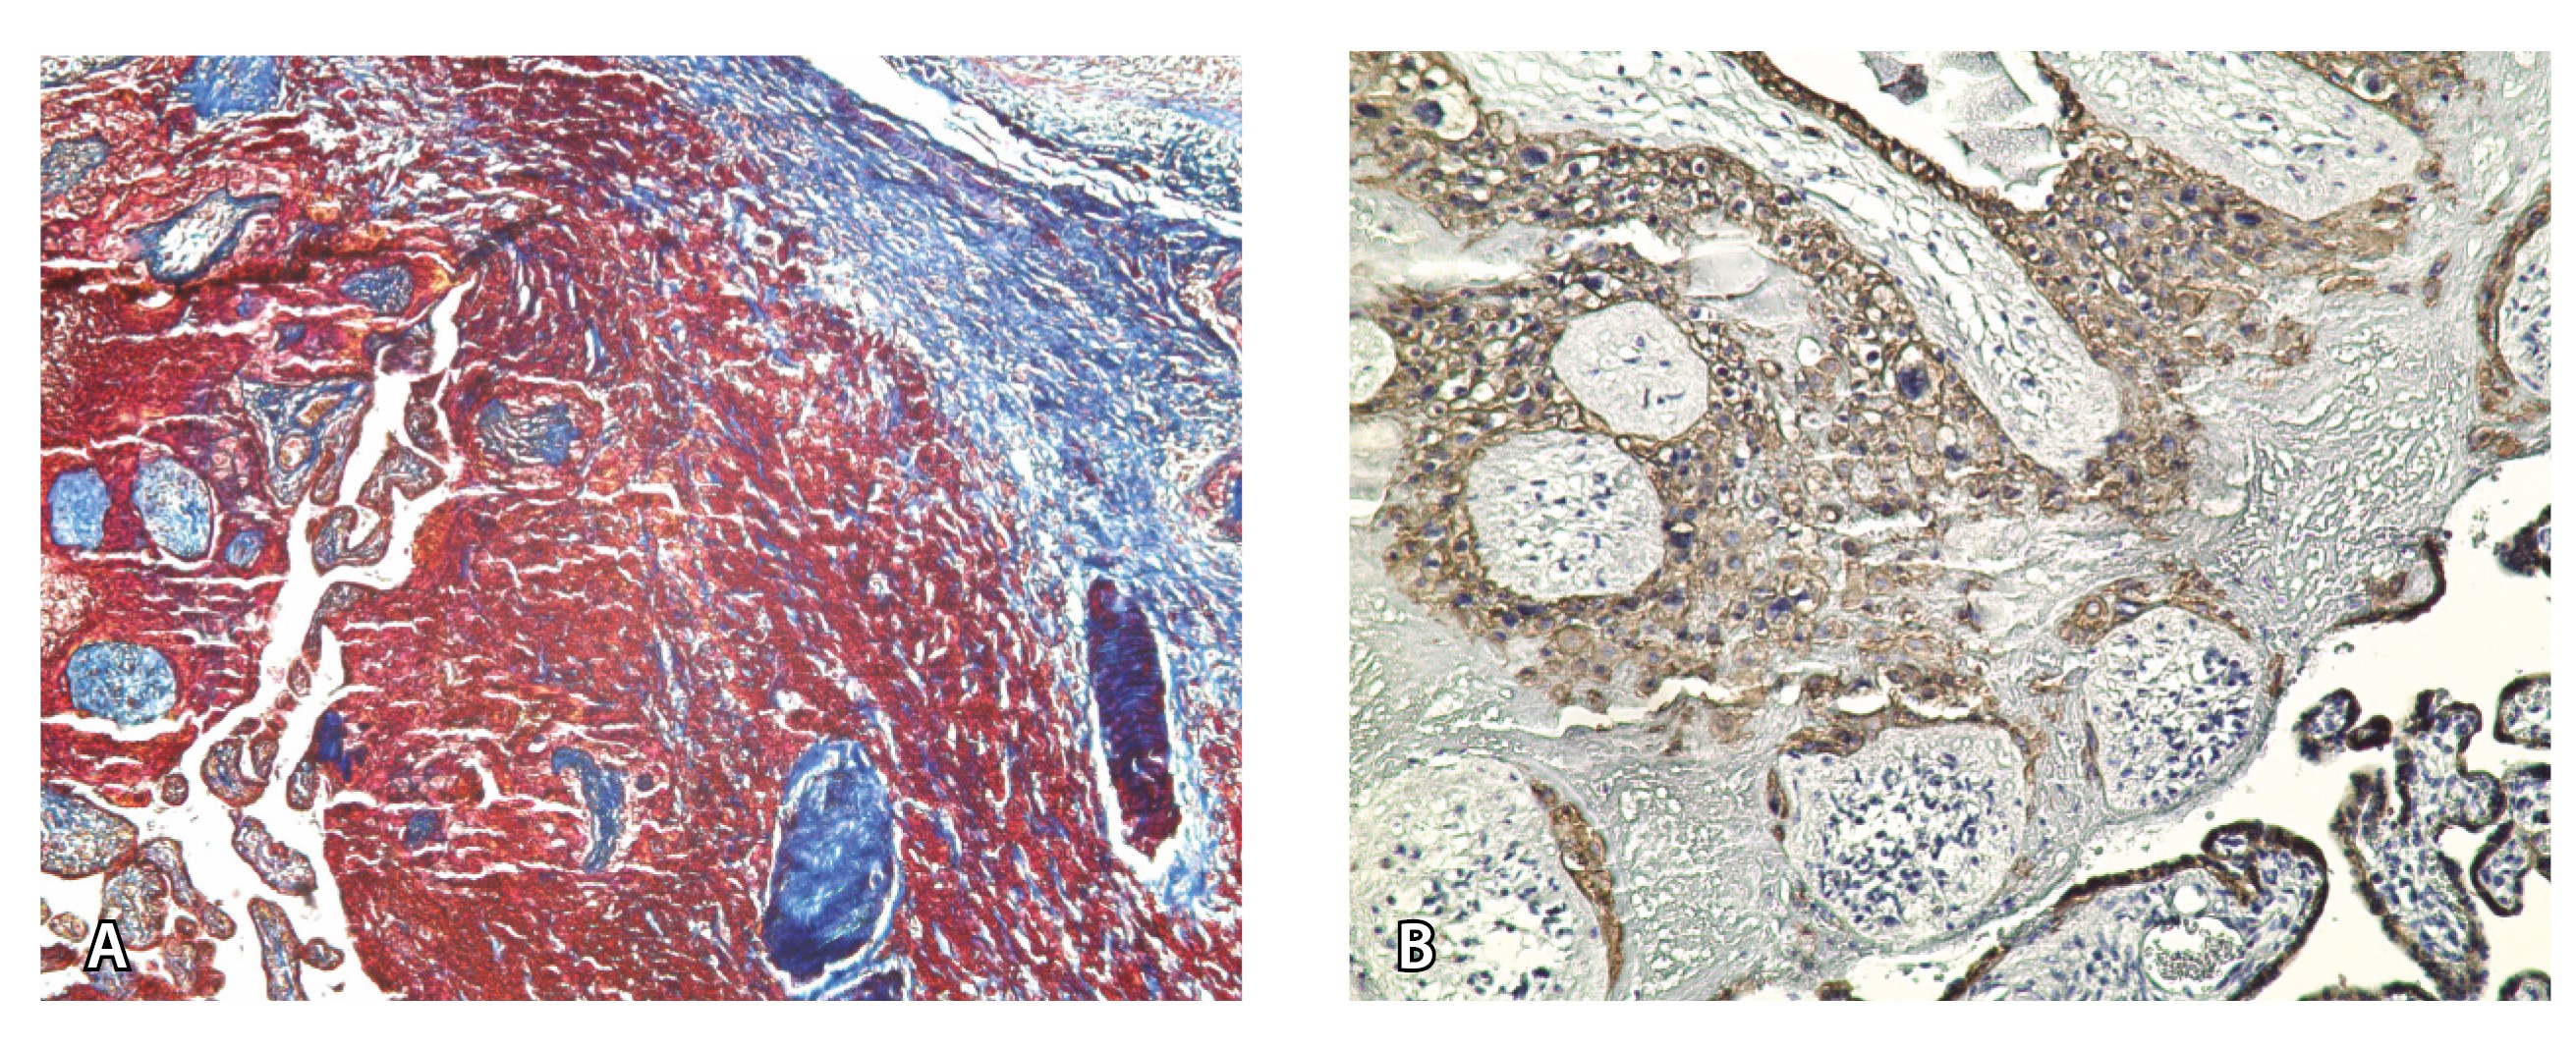

Сосуды 2-го типа. Единичные сливающиеся сосудистые полости в маточно-плацентарной области, мелкие ретроплацентарные гематомы, участки с белковым содержимым по МР-сигналу в зоне контакта ворсин со стенкой матки (рис. 4).

Рис. 4. Беременность 32 недели, pl. accreta, PAS 1 по FIGO. На магнитно-резонансных томограммах в режиме Т2-взвешенного изображения в сагиттальной (А) и аксиальной (Б) плоскостях видны сосуды на границе маточно-плацентарной области, сливающиеся между собой (белые стрелки), без выраженного дефицита толщины миометрия и рубца от кесарева сечения, без признаков выбухания стенки матки. На Т1-взвешенном изображении в режиме подавления сигнала от жировой ткани в аксиальной плоскости (В) выявляется наличие участков повышенного сигнала (желтые стрелки) на границе маточно-плацентарной области, что соответствует геморрагическому компоненту в подострой/хронической стадии (ретроплацентарные гематомы) либо белковому содержимому (фибриноид)

Непосредственное сравнение МР-картины с операционным материалом подтвердило, что полости с геморрагическим компонентом соответствовали ретрохориальным гематомам различной давности, чаще подострой и хронической стадий, которые состояли из гемолизированных эритроцитов, нитей фибрина сетчатого строения, а также замурованных атрофичных ворсин (рис. 5). Следовательно, констатация на МРТ фиксированных геморрагических полостей в маточно-плацентарной области отражает не гиперваскуляризацию стенки матки, а наличие ретрохориальных гематом в подострой/хронической стадии, что следует учитывать в клинической практике.

Рис. 5. Сосуды 2-го типа при гиперваскуляризации стенки матки при патологической инвазии: А – организованная ретрохориальная гематома в маточно-плацентарной области, в ее составе много инволютивных якорных ворсин (окраска по Маллори; × 100); Б – в составе гематомы видна пролиферация цитотрофобласта (иммуногистохимическое исследование, маркер цитокератин 8; × 100)

Как видно на рис. 6, сосуды 2-го типа не встречались в норме и при плотном прикреплении плаценты (gr 2), с одинаковой частотой наблюдались при pl. accreta (gr 3) и pl. increta (gr 4) и были обнаружены у 94,4% пациенток с pl. percreta (gr 5) (р < 0,001, хи-квадрат Пирсона).

Сосуды 2-го типа не встречались в норме и при плотном прикреплении плаценты, что говорит об их специфичности для приращения плаценты. Данные сосуды выявлялись при pl. accreta (52,9%), pl. increta (50%) и pl. percreta (94,4%). Они представляли собой сливающиеся сосудистые полости в маточно-плацентарной области, мелкие ретрохориальные (ретроплацентарные) гематомы, участки с белковым содержимым, что, по данным патоморфологического исследования, может соответствовать увеличению количества плодного фибриноида. Считается, что именно фибриноид служит дополнительным фактором, способствующим инвазии трофобласта и активному ангиогенезу в стенке матки [16]. Учитывая, что данный тип сосудов встречался чаще остальных вариантов сосудов в группе пациенток с pl. accretа, полагаем, что он является патогномоничным для данной глубины врастания плаценты. В то же время при глубокой инвазии по типу pl. increta и pl. percreta характерно сочетание данного типа сосудов с сосудами, описанными ниже.